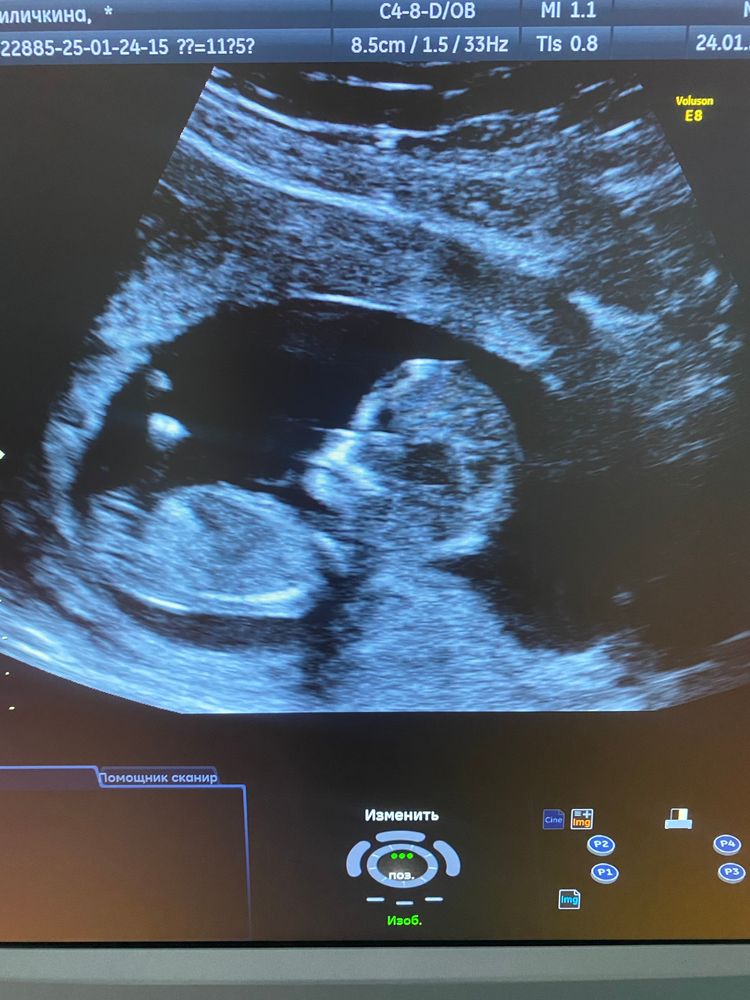

Хорошие или плохие не знаю, меня устроили ☺️ Малыша видно.

Но в 15 недель я ходила на УЗИ на хороший аппарат. Мне выдали очень неплохой снимок в 3Д, а вот 2Д совсем неудачный получился.

Малыш согнутый лежал, там даже не сразу понятно, где голова 😅